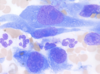

what inflammation is shown here

granulomatous inflammation